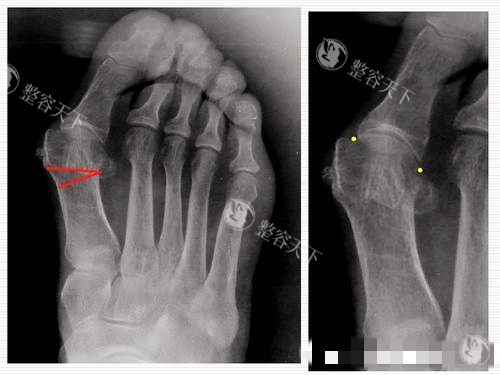

“李医生,我这脚歪了十年,还能救吗?”56岁的王阿姨攥着X光片,脚上第二脚趾已经翘得像“小锤子”。李昕宇推了推眼镜,指着片子:“拇外翻角45度,跖骨内收,得用三代Scarf截骨+Akin术式。”

这位北京中医药大学第三附属医院的副主管医师,专攻足踝外科20年,手术刀下“救”过3000多双脚。他的绝活是“所见即所得”——术前用双足负重CT扫描,把足部骨骼像拼乐高一样三维重建,截骨角度误差控制在±1度内,术后拇趾力线能精细回到生理角度。